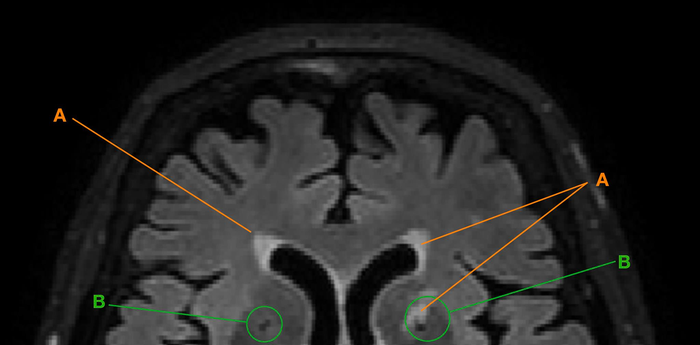

White spots and black holes

In her PhD thesis, first author Isabel Hotz used novel automatic methods among others to study so-called lacunes and white matter hyperintensities. These degenerative processes showed up as “black holes” and “white spots” on the digital images. The reasons for this are not yet known and may have to do with small, unnoticed cerebral infarcts, reduced blood flow or loss of nerve pathways or neurons. This can limit a person’s cognitive performance, in particular when degeneration affects key regions of the brain.